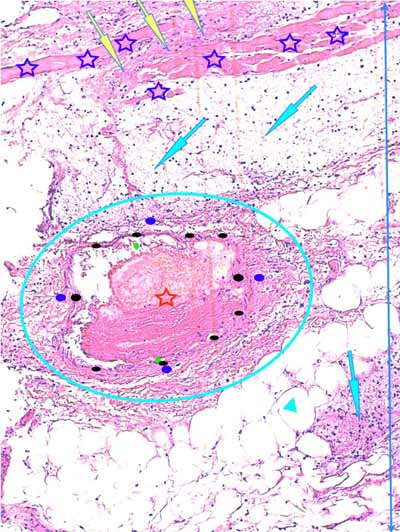

Photo 8 (Hémalun-Eosine X100) : le muscle peaucier présente des zones de nécrose

de liquéfaction. Les lobules adipeux de l’hypoderme et les myofibrilles du muscle peaucier

sont dilacérés par un infiltrat exsudatif de granulocytes neutrophiles. La lumière

d’une veine de moyen calibre est obstruée par un thrombus fibrineux.

Légendes de la Photo 8 :

- Flèches jaunes : zone de nécrose de liquéfaction du muscle peaucier

- Flèches turquoises : œdème et infiltrat neutrophilique dilacérant les adipocytes des lobules adipeux de l’hypoderme

- Pointe de flèche turquoise : adipocyte

- Ovale turquoise : veine de moyen calibre

- Ronds verts : endothélium de la veine

- Ronds noirs : media de la veine

- Ronds bleus : adventice de la veine

- Double flèche bleue : hypoderme

- Étoile rouge : thrombus fibrineux ostruant la lumière de la veine

- Étoiles bleues : myofibrilles du muscle peaucier